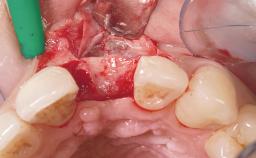

Immediate Placement of an Implant in a Maxillary Left Central Incisor Site

| Bone Augmentation | Horizontal|Simultaneous |

| Augmentation Materials | Xenogenous|Membrane |

| Soft Tissue Grafting | Simultaneous |